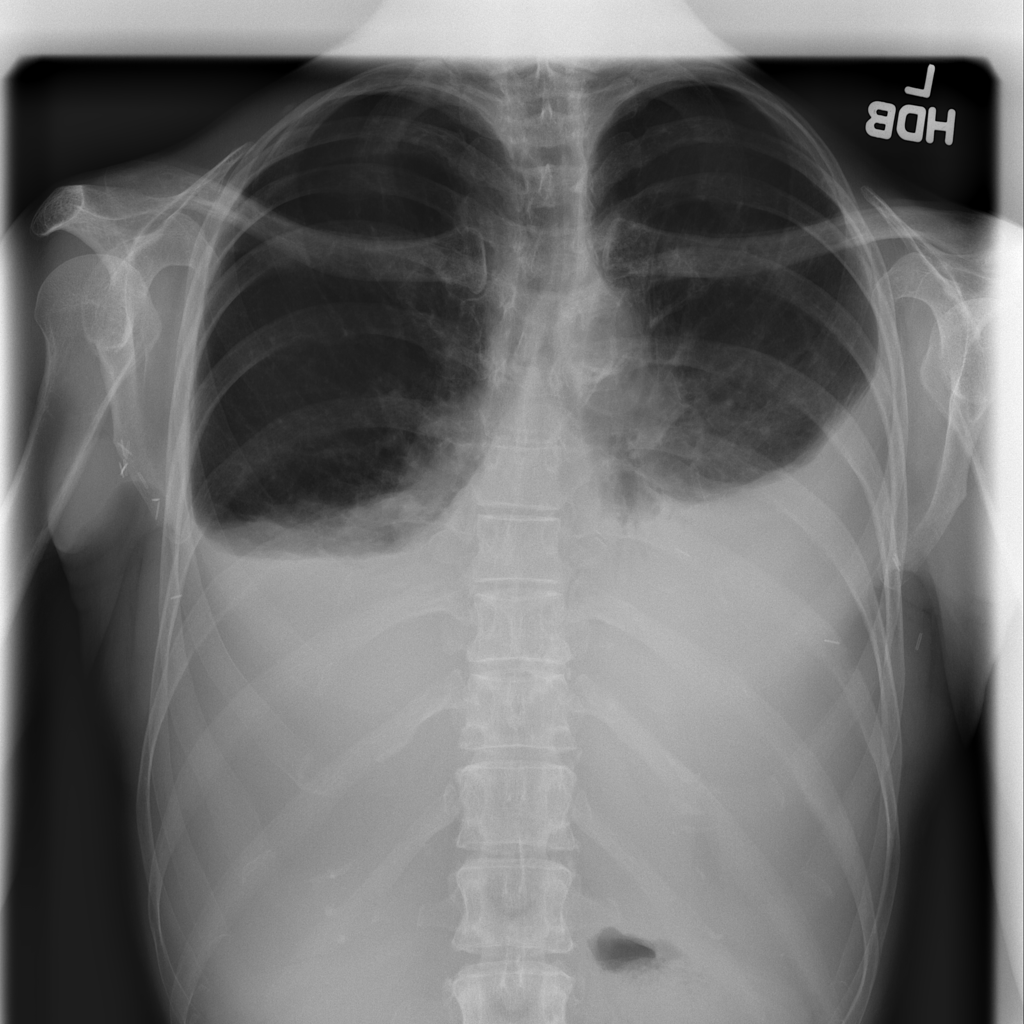

PAT-4639 · IMG-021Effusion

PAT-4639 · IMG-021

PA